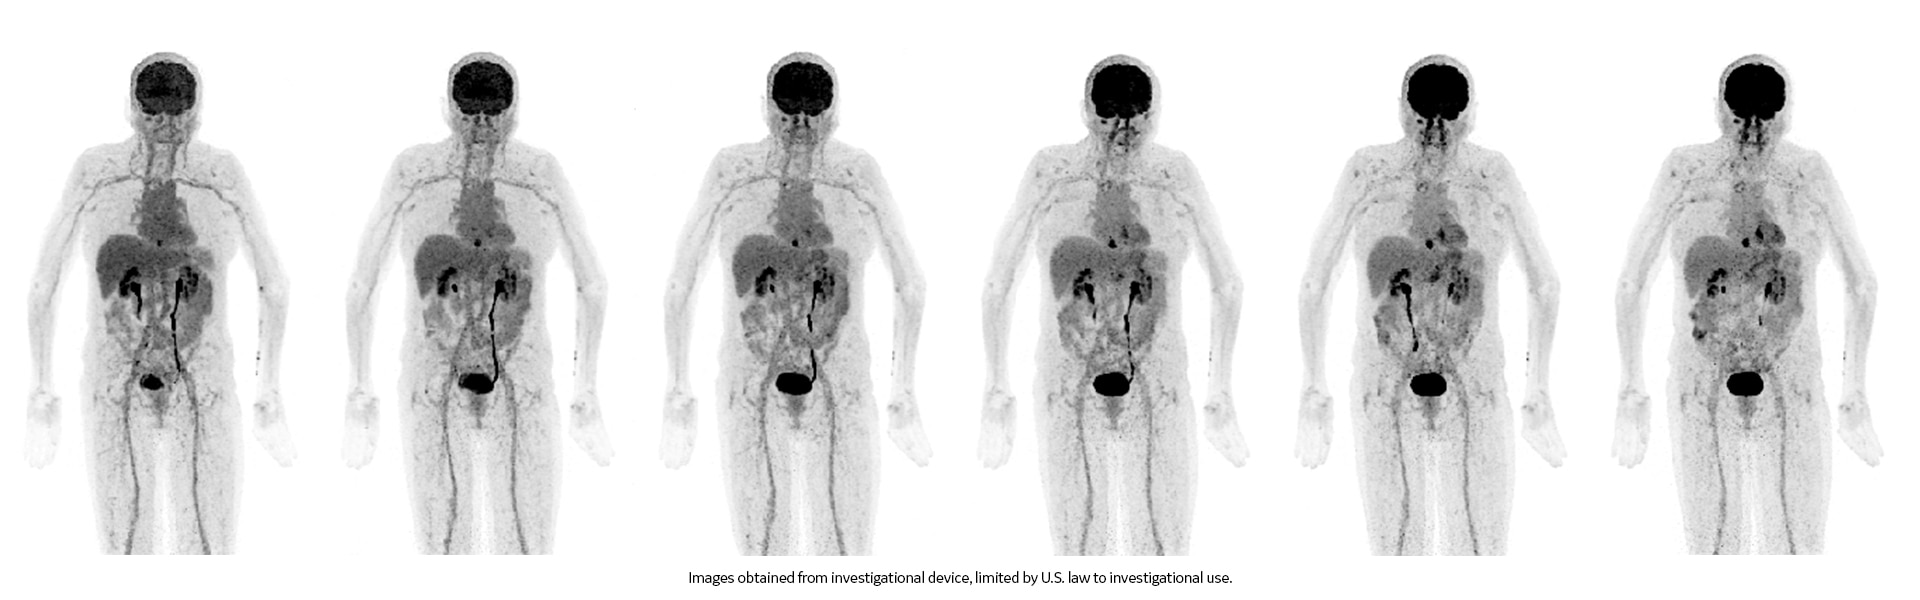

Images cliniques

Lésions multiples au niveau des jambes et du cou

Petite lésion de l'oreille et tumeur de la hanche.

Lésion cervicale à droite mesurant 6 mm.

Acnée visible sur le dos

Poumon droit, aine droite et tumeur derrière le genou droit.

Cancer de la tête et du cou.

Évolution du cancer après la radiothérapie. Minuscule cancer du sein.

Ganglions lymphatiques avec fixation de FDG au niveau de l’aisselle gauche (vaccination contre la COVID-19).